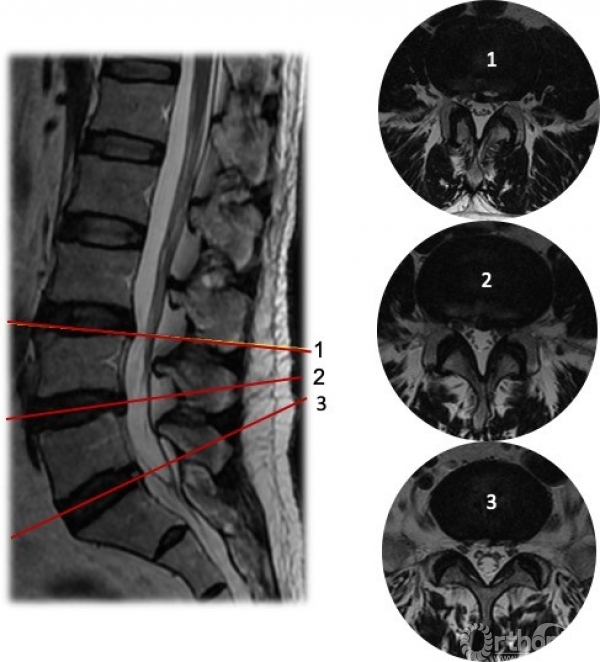

入院诊断:腰椎间盘突出症(L3-S1);腰椎管狭窄症;左肾输尿管恶性肿瘤术后;慢性乙型肝炎;高血压3级(极高危);冠状动脉粥样硬化性心脏病。

困惑:患者存在多节段腰椎间盘突出,同时神经根定位存在混杂,同时患者年龄大、基础疾病多、一般身体状况较弱,大开放减压手术耐受性差,但因疼痛剧烈,患者强烈要求手术治疗,解除疼痛。

图4 术前MRI

解决方案:根据主诉、查体、辅助检查,术前需要明确致痛节段。首先,予患者局麻下行腰椎间盘造影(L2/3,L3/4,L4/5)(图5),在L3/4节段注射造影剂约2ml时,诱发出患者下腰痛症状,继续注射造影剂增加盘内压力后复制出左下肢放射痛,考虑该节段椎管空间狭小,遂予L4/5节段左椎间孔行L4出口神经根选择性神经根封闭,后患者左下肢疼痛明显缓解。

患者约2天后左下肢疼痛复现,遂于局麻下为患者实施了L3/4经皮内镜下腰椎间盘切除术,术中发现神经根与纤维环粘连,松解粘连,术后患者疼痛得到完全缓解。左侧直腿抬高试验与股神经牵拉试验转阴。术前后核磁可见该节段神经压迫解除。(图6)